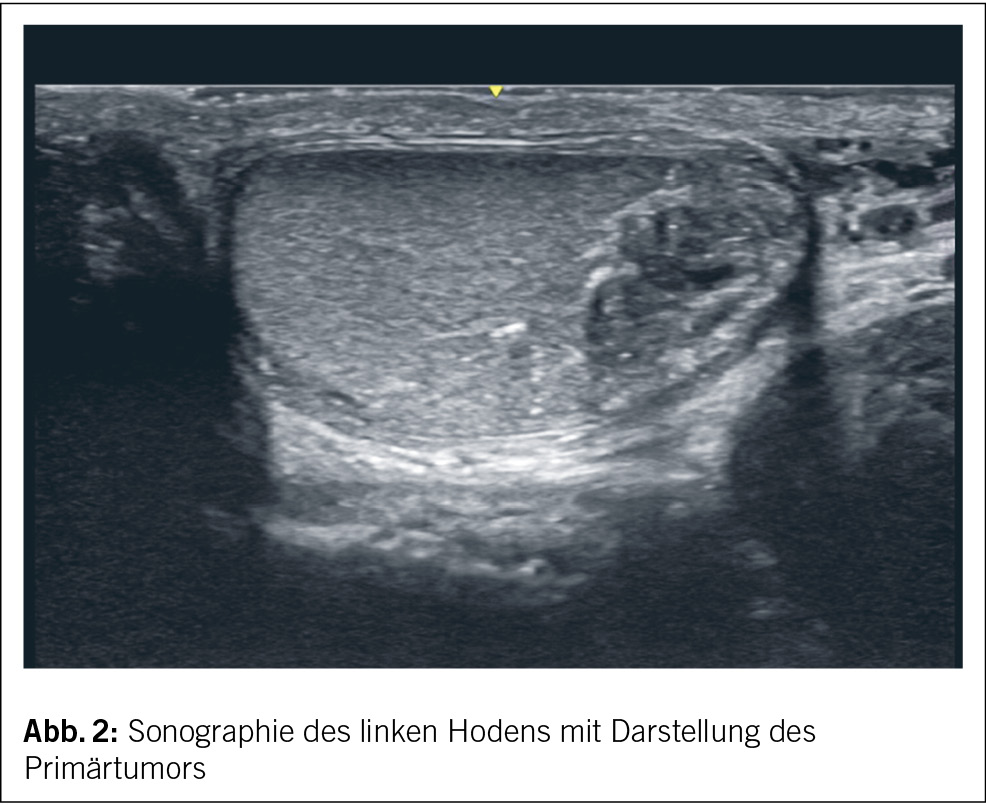

Zur weiteren Abklärung erfolgte ergänzend eine Sonographie des restlichen Abdomens ohne weitere Pathologien sowie eine Sonographie des Hodens mit Nachweis eines möglichen Primärtumors im linken Hoden (Abb. 2).

In der ergänzend durchgeführten Computertomographie des Thorax und Abdomens wurde der sonographisch und laboranalytische Verdacht im Sinne eines Hodentumors mit grosser retroperitonealer Lymphknotenmetastase bestätigt und der Patient den Kollegen der Urologie und Onkologie zugewiesen.

Der Keimzelltumor ist bei Männern zwischen 20 und 44 Jahren die häufigste maligne Tumorerkrankung. Der Anteil an allen malignen Erkrankungen in dieser Altersspanne beträgt etwa 25 %. In den letzten Jahren konnte in allen industrialisierten Ländern eine Zunahme der Diagnose von Keimzelltumoren beobachtet werden (2). Die Inzidenz in der Schweiz betrug 2016 etwa 12/100 000, womit die Schweiz zu den Ländern mit der höchsten Inzidenz gehört (3). Zwischenzeitlich zeigte sich 2021 eine Zunahme der Inzidenz in anderen europäischen Ländern. Im Durchschnitt erkrankten zwischen 2013 und 2017 pro Jahr rund 470 Männer an Hodenkrebs (4). Bekannte Risikofaktoren sind etwa der Maldeszensus testis, Unfruchtbarkeit oder eine positive Familienanamnese (5, 6). Gemäss den deutschen Leitlinien wird ein routinemässiges Screening nicht empfohlen, ausser bei entsprechenden Risikofaktoren oder auffälligen Veränderungen bei der Selbstuntersuchung (7). Bei entsprechendem klinischen Verdacht empfehlen die deutschen S3-Leitlinien die bilaterale Hodensonographie mit einer planaren Sonde mit mindestens 7.5 MHZ (S3-Leitlinie Diagnostik, Therapie und Nachsorge der Keimzelltumoren des Hodens, Februar 2020). Ergänzend sollte ein CT Thorax-Abdomen-Becken zum Staging durchgeführt werden. Die S3-Leitlinien empfehlen zusätzlich die Abnahme der Tumormarker Beta-HCG, AFP und LDH sowohl präoperativ wie auch postoperativ zur Therapiekontrolle und Bestimmung des für die Stadieneinteilung wichtigen postoperativen Nadirs (7). Bei rund der Hälfte der Patienten sind Tumormarker erhöht (8). Die Tumormarker dienen dabei nicht nur der Stadieneinteilung, sondern auch der Unterscheidung zwischen Chorionkarzinomen, reinen Seminomen und Nichtseminomen. So spricht etwa das Vorliegen erhöhter AFP-Werte wie in unserem Fall gegen das Vorliegen eines reinen Seminoms (9). LDH hingegen ist unspezifisch, korreliert jedoch mit der Prognose. LDH ist in 80 % aller Patienten mit fortgeschrittenen, metastasierten Keimzelltumoren erhöht (7).

Die Überlebensrate ist im Vergleich zu anderen Krebserkrankungen sehr gut. Die 10-Jahres-Überlebensrate beträgt bis 95 % (2). Bei metastasierten Tumoren in der Poor-Prognosis-Group liegt die 5-Jahres-Überlebenswahrscheinlichkeit bei 48–64 % (10, 11). Zusammenfassend ist es wichtig, bei entsprechendem klinischen Verdacht eine umfassende Untersuchung und Organisation der Behandlung einzuleiten. Eine interdisziplinäre Zusammenarbeit mit den Kollegen der Onkologie und Urologie ist dabei von zentraler Bedeutung. Der Fall repräsentiert deutlich auch den Stellenwert der Sonographie für die Notfall- wie auch Hausarztmedizin.